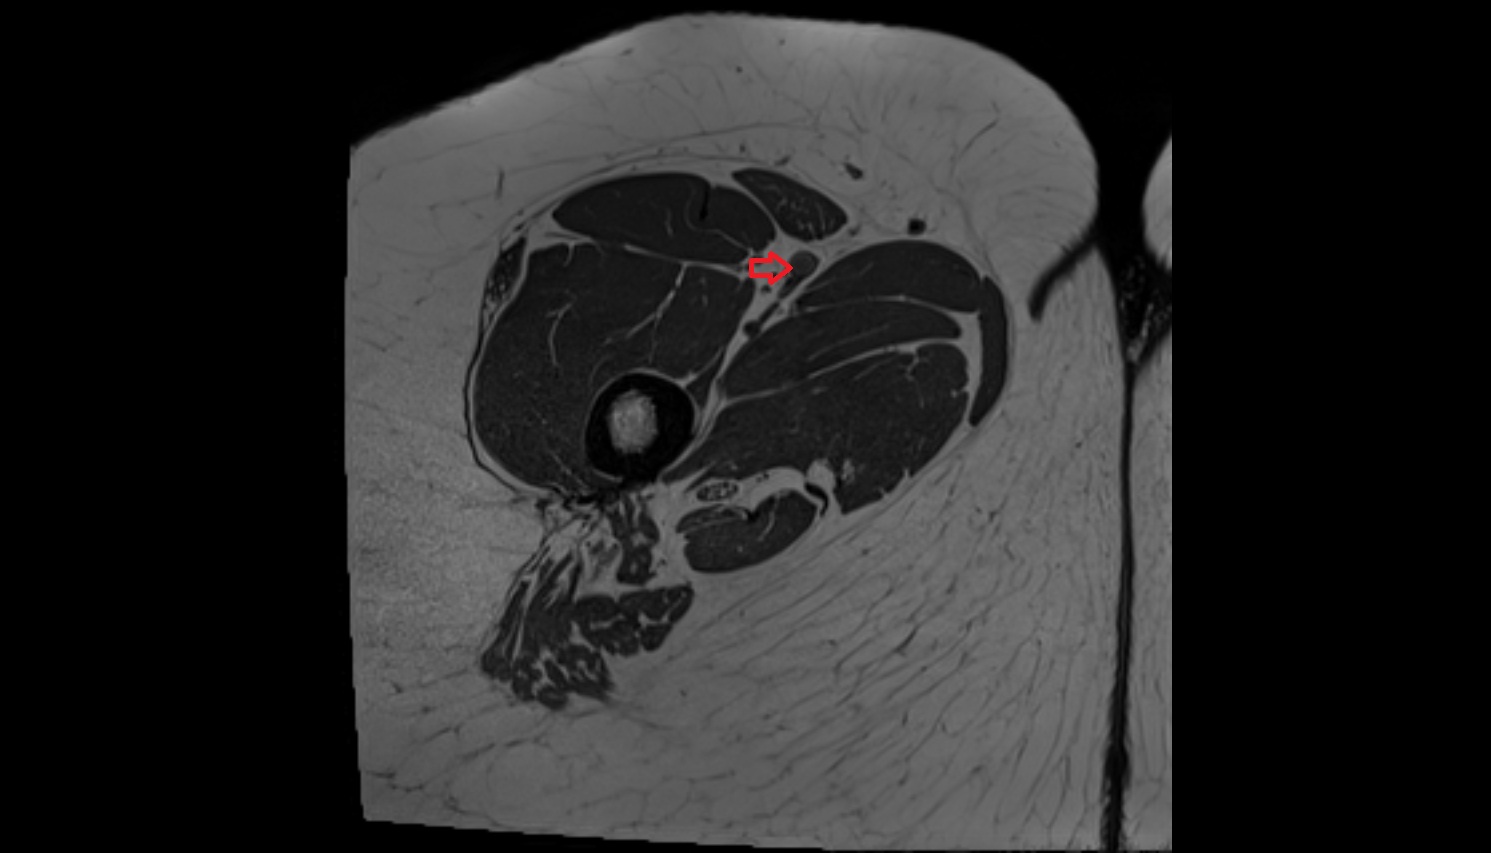

- Deep femoral artery (profunda femoris)

- Femoral artery

- Superficial femoral artery

- Deep femoral vein (profunda femoris vein)